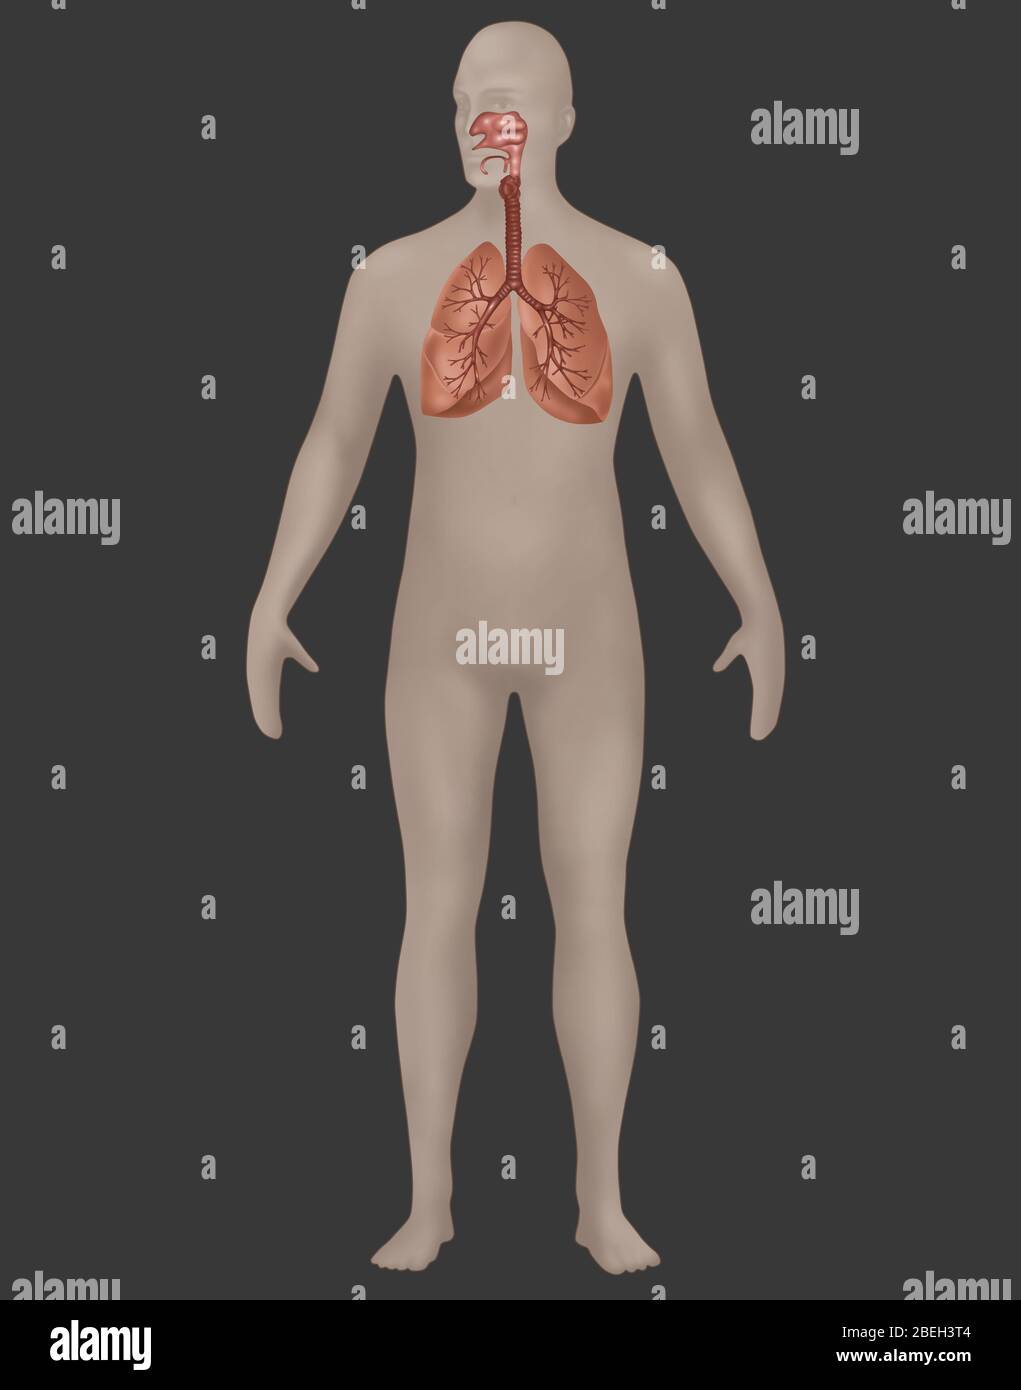

Männchen anatomie Stockfotos & Bilder

RFHT54Y0–Männliche Anatomie. Skelett und hervorgehobenen Lungen. 3D Illustration. Clipping-Pfad enthält.

Suchergebnisse für Männchen anatomie Stock-Fotos & Bilder (86,080)